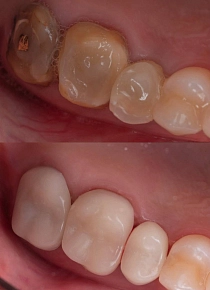

Зуб сильно разрушился, можно ли избежать удаления?